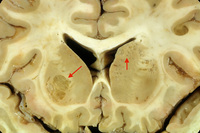

Corte coronal do cérebro de paciente com meningoencefalite criptocócica exibindo aparência clássica de estruturas de "bolha de sabão" nos gânglios da base (setas) resultando de expansão criptocócica de espaços de Virchow-Robbin em volta dos vasos lenticuloestriados

Do acervo pessoal de Robert E. Schmidt; usado com permissão